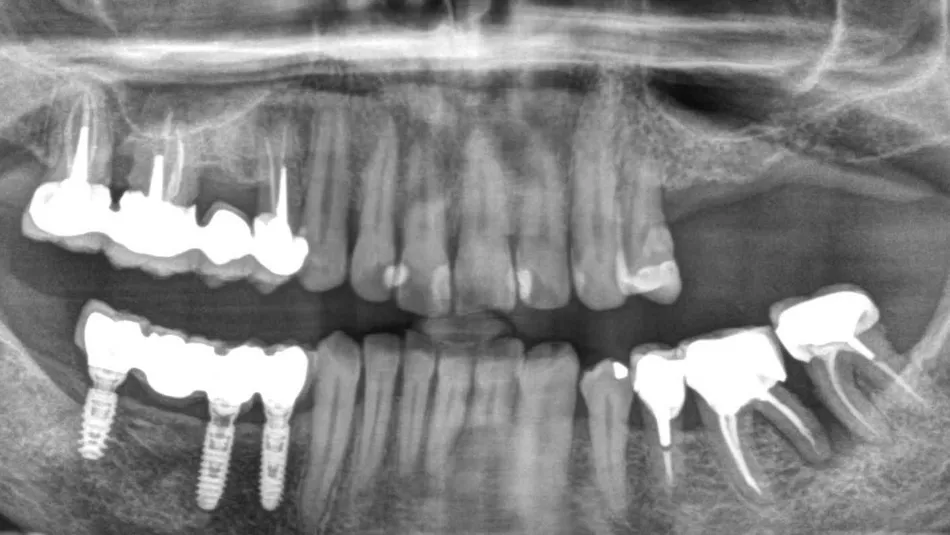

1-2. Panoramic radiography and cone-beam computed tomography showing vertical bone loss. With only 4 mm of sinus floor bone, implant placement was not feasible.

16. Postoperative panoramic radiograph.